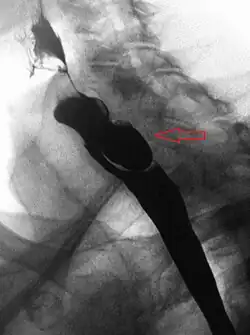

A Zenker's diverticulum, also pharyngeal pouch, is a diverticulum of the mucosa of the human pharynx, just above the cricopharyngeal muscle (i.e. above the upper sphincter of the esophagus). It is a pseudo diverticulum or false diverticulum (only involving the mucosa and submucosa of the esophageal wall, not the adventitia), also known as a pulsion diverticulum.

When there is excessive pressure within the lower pharynx, the weakest portion of the pharyngeal wall balloons out, forming a diverticulum which may reach several centimetres in diameter.

While traction and pulsion mechanisms have long been deemed the main factors promoting development of a Zenker's diverticulum, current consensus considers occlusive mechanisms to be most important: uncoordinated swallowing, impaired relaxation and spasm of the cricopharyngeus muscle lead to an increase in pressure within the distal pharynx, so that its wall herniates through the point of least resistance (known as Killian's triangle, located superior to the cricopharyngeus muscle and inferior to the thyropharyngeus muscle. Thyropharyngeus and cricopharyngeus are the superior and inferior parts of inferior constrictor muscle of pharynx respectively). The result is an outpouching of the posterior pharyngeal wall, just above the esophagus.[3]

A combination of the simple barium swallow and a thorough endoscopy will normally confirm the diverticulum.[4]